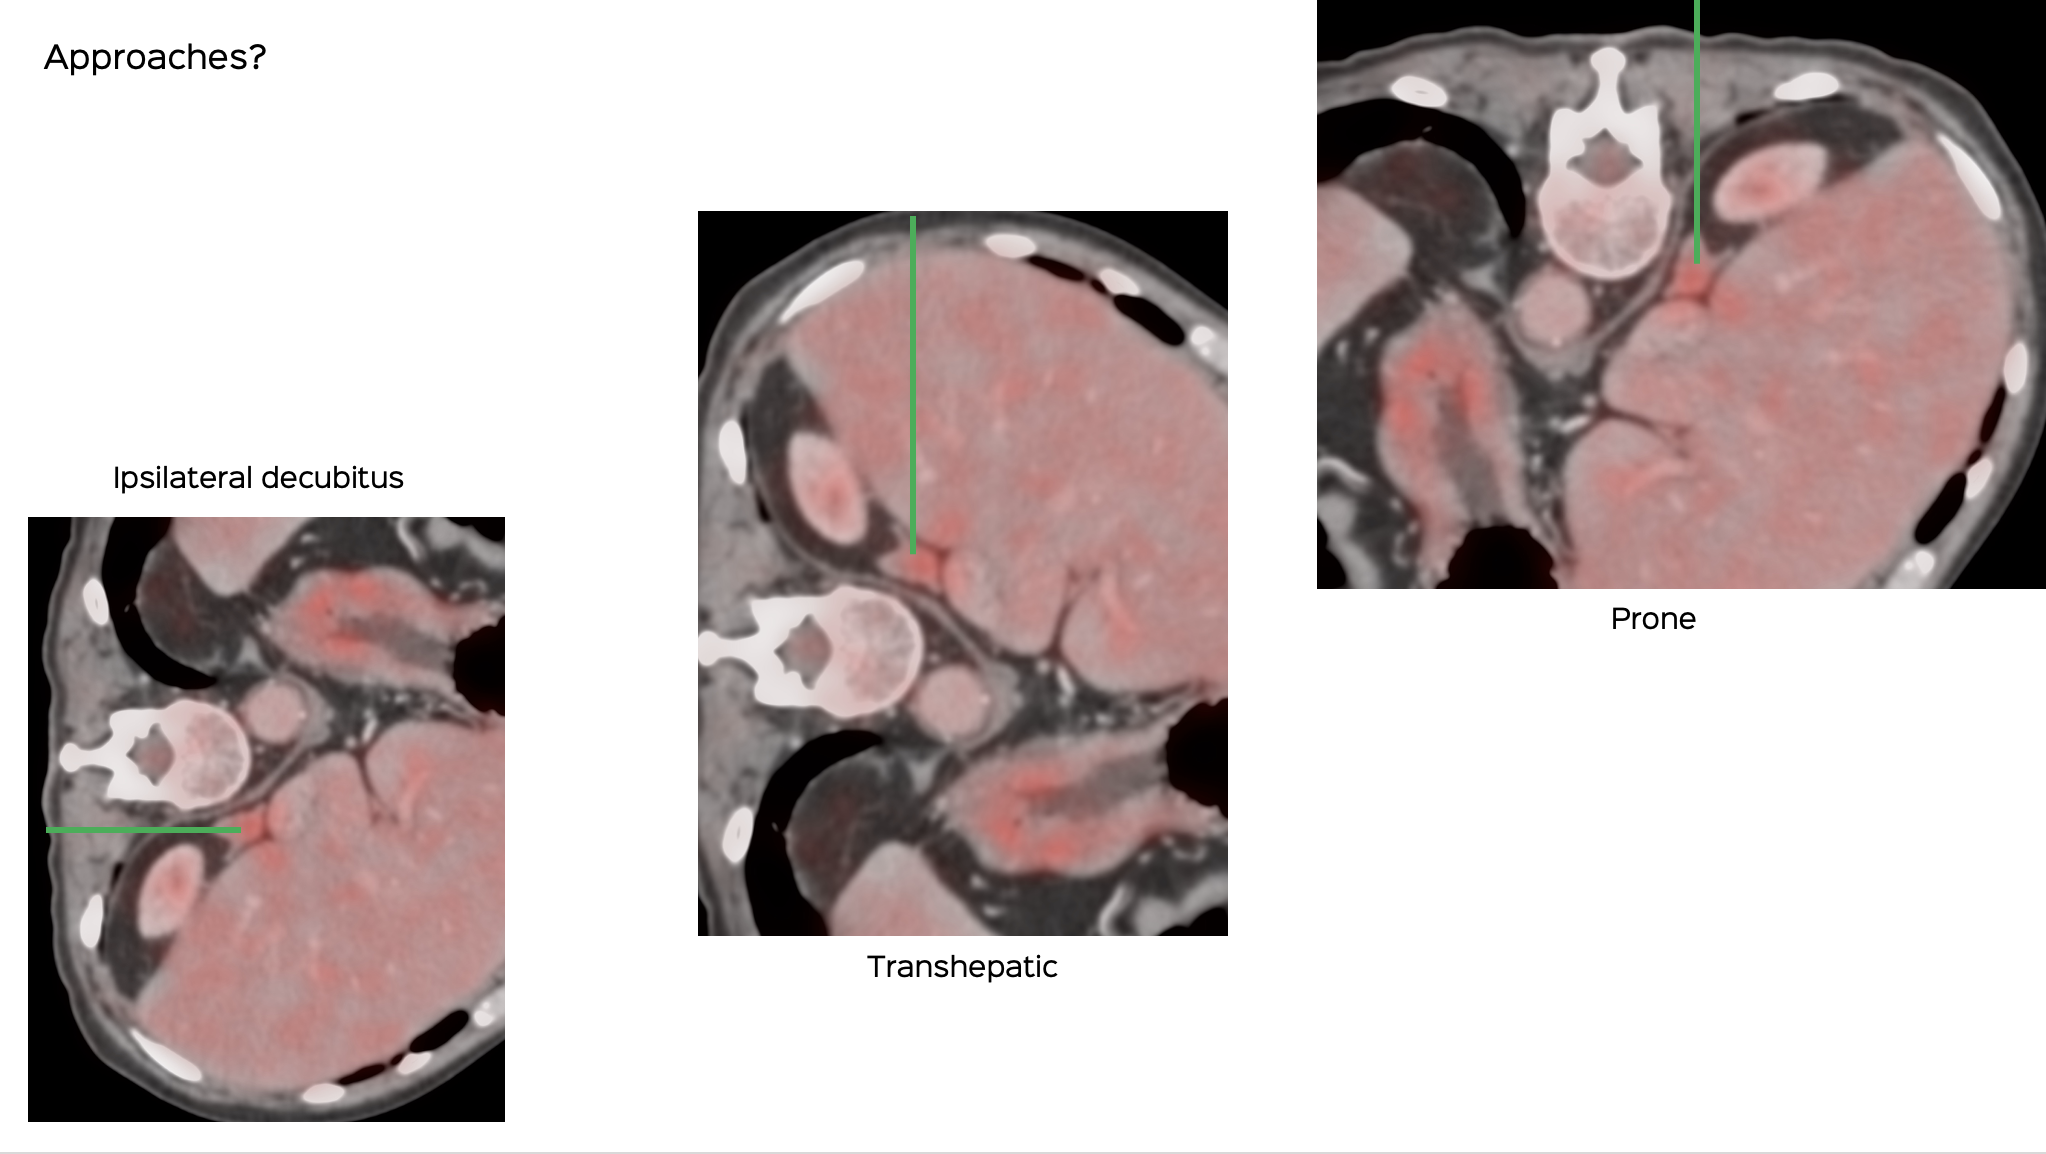

What would be your approach?

The video below describes the case, why none of these approaches worked, but what was done finally was a biopsy using an ipsilateral up approach with hydrodissection.

Position & Approach: left lateral decubitus - first prone, then rt lateral decubitus, then left plus hydrodissection, extrapleural